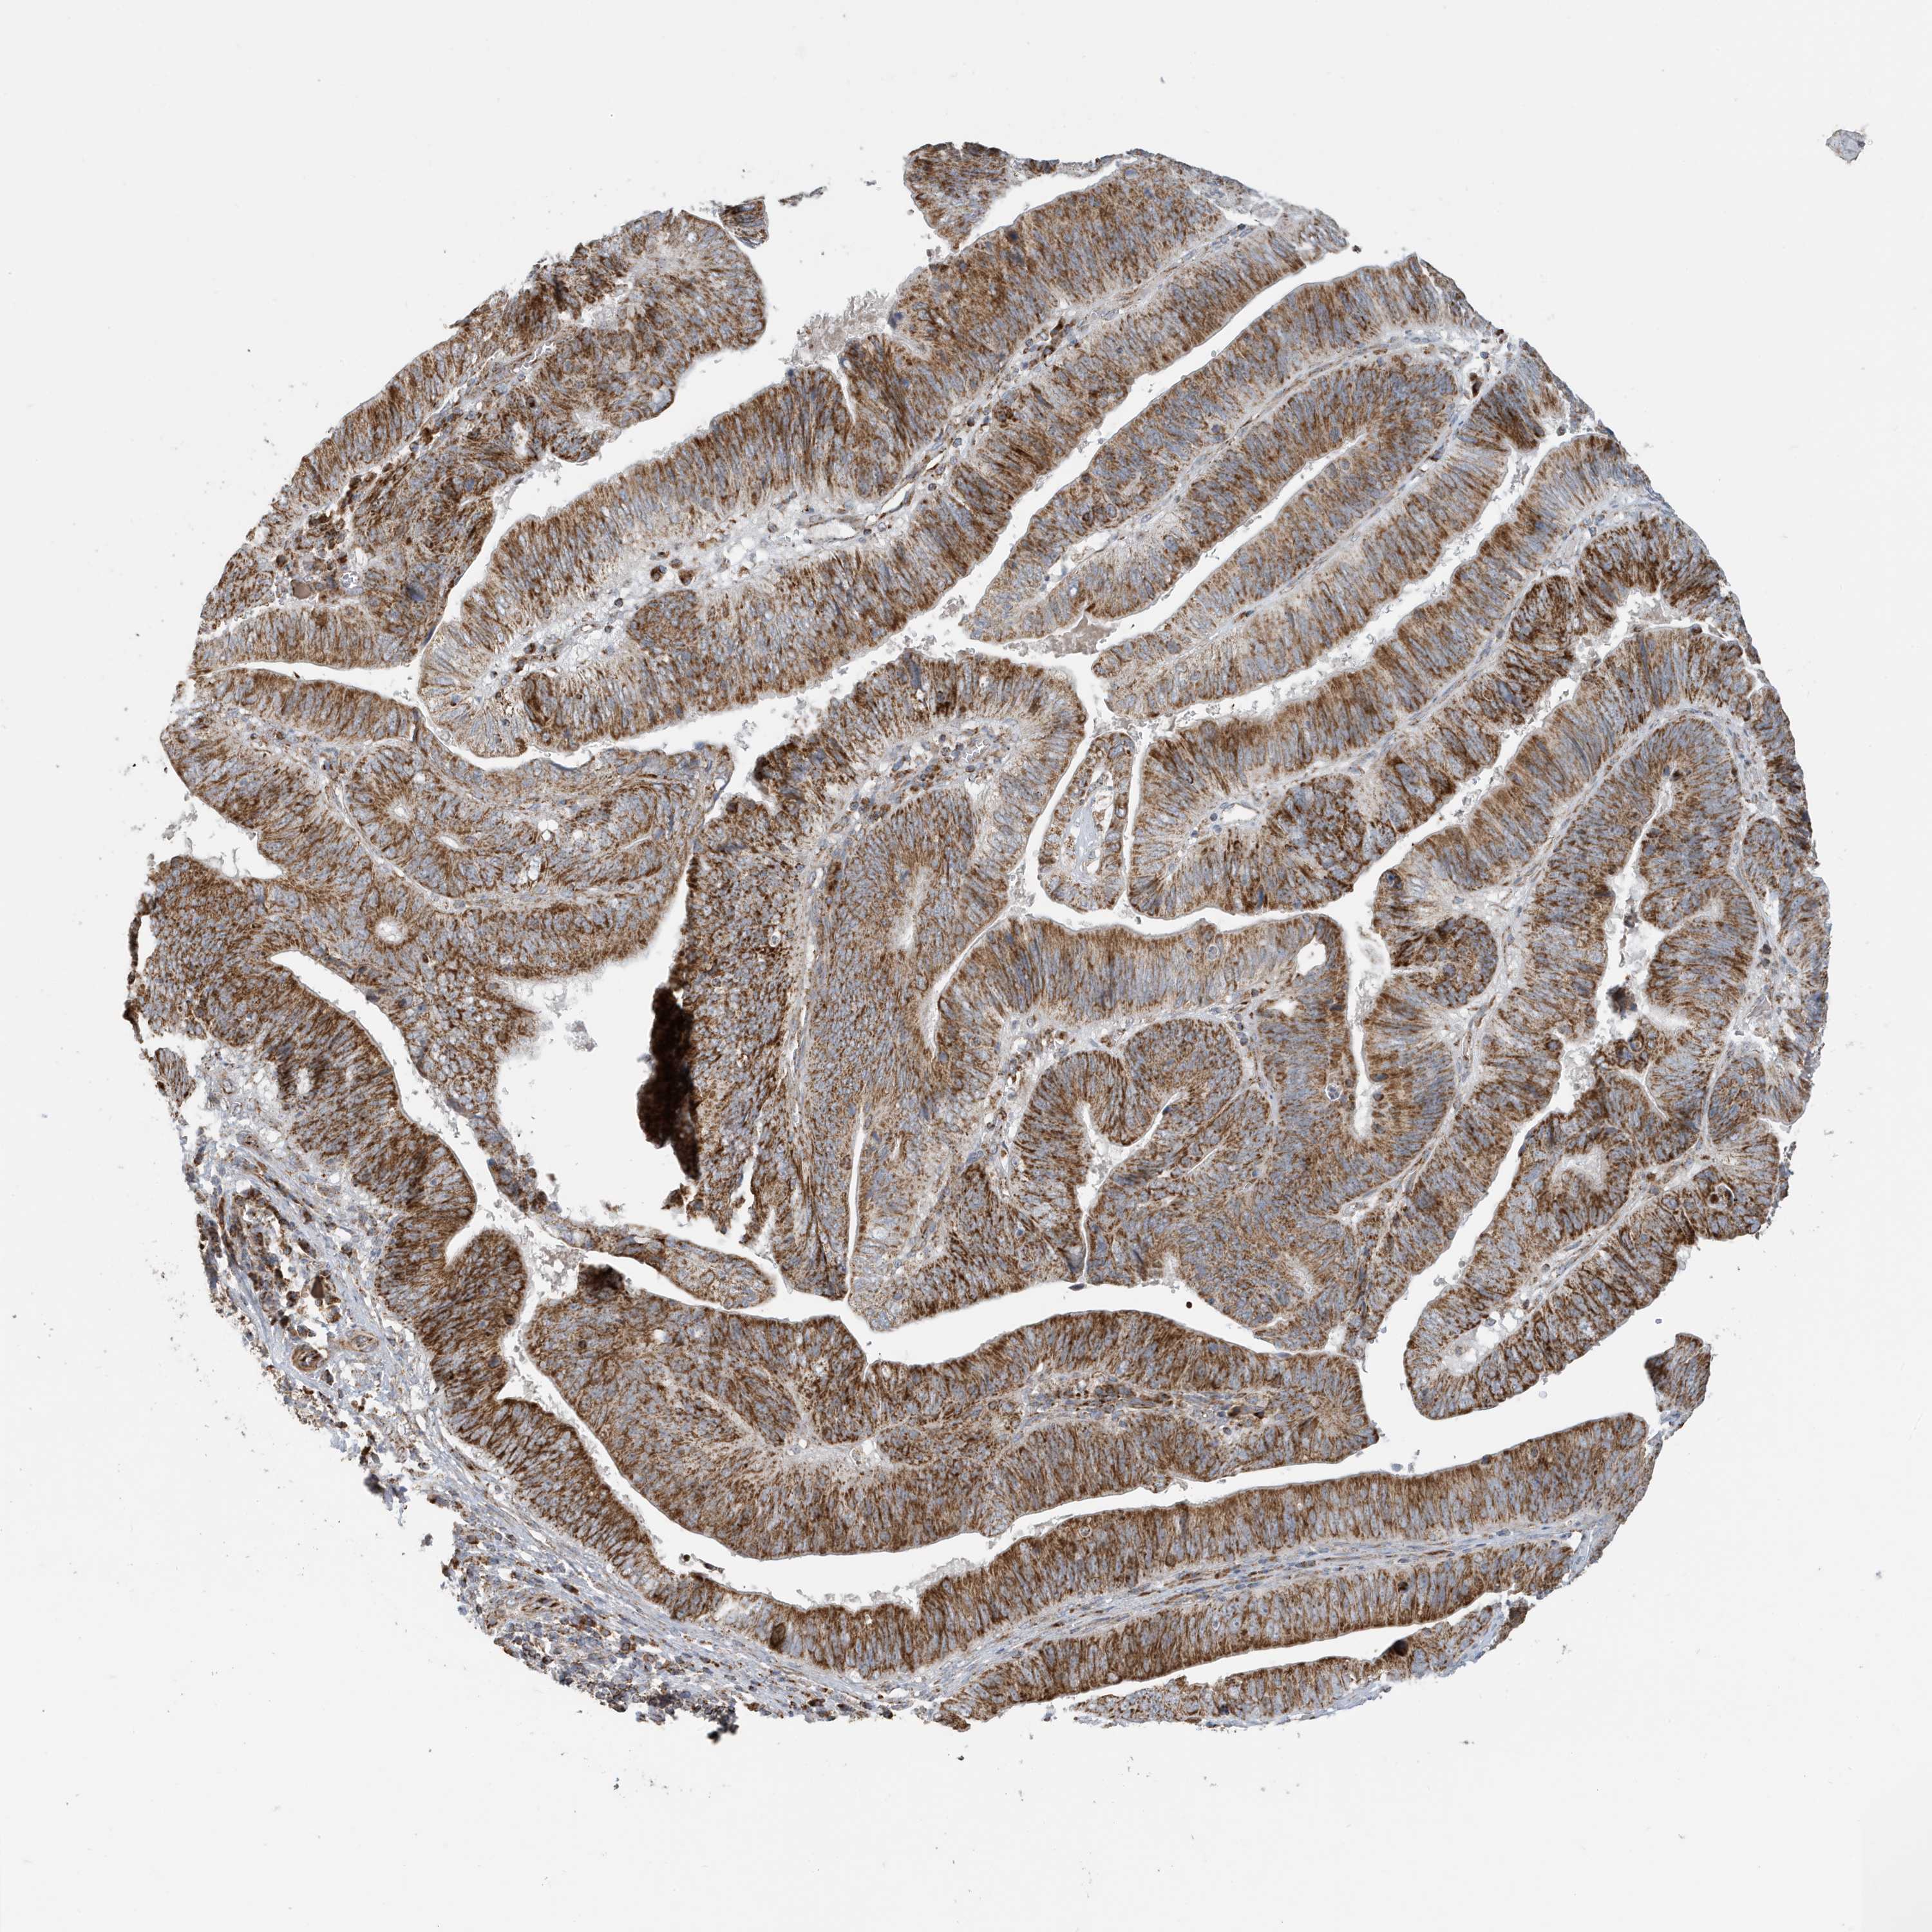

PANCREATIC CANCER - Protein expressioni

A mouse-over function shows sample information and annotation data. Click on an image to view it in a full screen mode. Samples can be filtered based on level of antibody staining by selecting one or several of the following categories: high, medium, low and not detected. The assay and annotation is described here.

Note that samples used for immunohistochemistry by the Human Protein Atlas do not correspond to samples in the TCGA dataset.

Antibody stainingi

Antibody staining in the annotated cell types in the current human tissue is reported as not detected, low, medium, or high, based on conventional immunohistochemistry profiling in selected tissues. This score is based on the combination of the staining intensity and fraction of stained cells.

Each image is clickable and will lead to virtual microscopy that enables deeper exploration of all samples and also displays staining intensity scores, fraction scores and subcellular localization as well as patient and tissue information for each sample.

Antibody HPA053198

Antibody HPA063561

Antibody CAB037058

Staining

High

Medium

Low

Not detected

Intensity

Strong

Moderate

Weak

Negative

Quantity

>75%

75%-25%

<25%

None

Location

Nuclear

Cytoplasmic/membranous

Cytoplasmic/membranous,nuclear

Adenocarcinoma, NOS